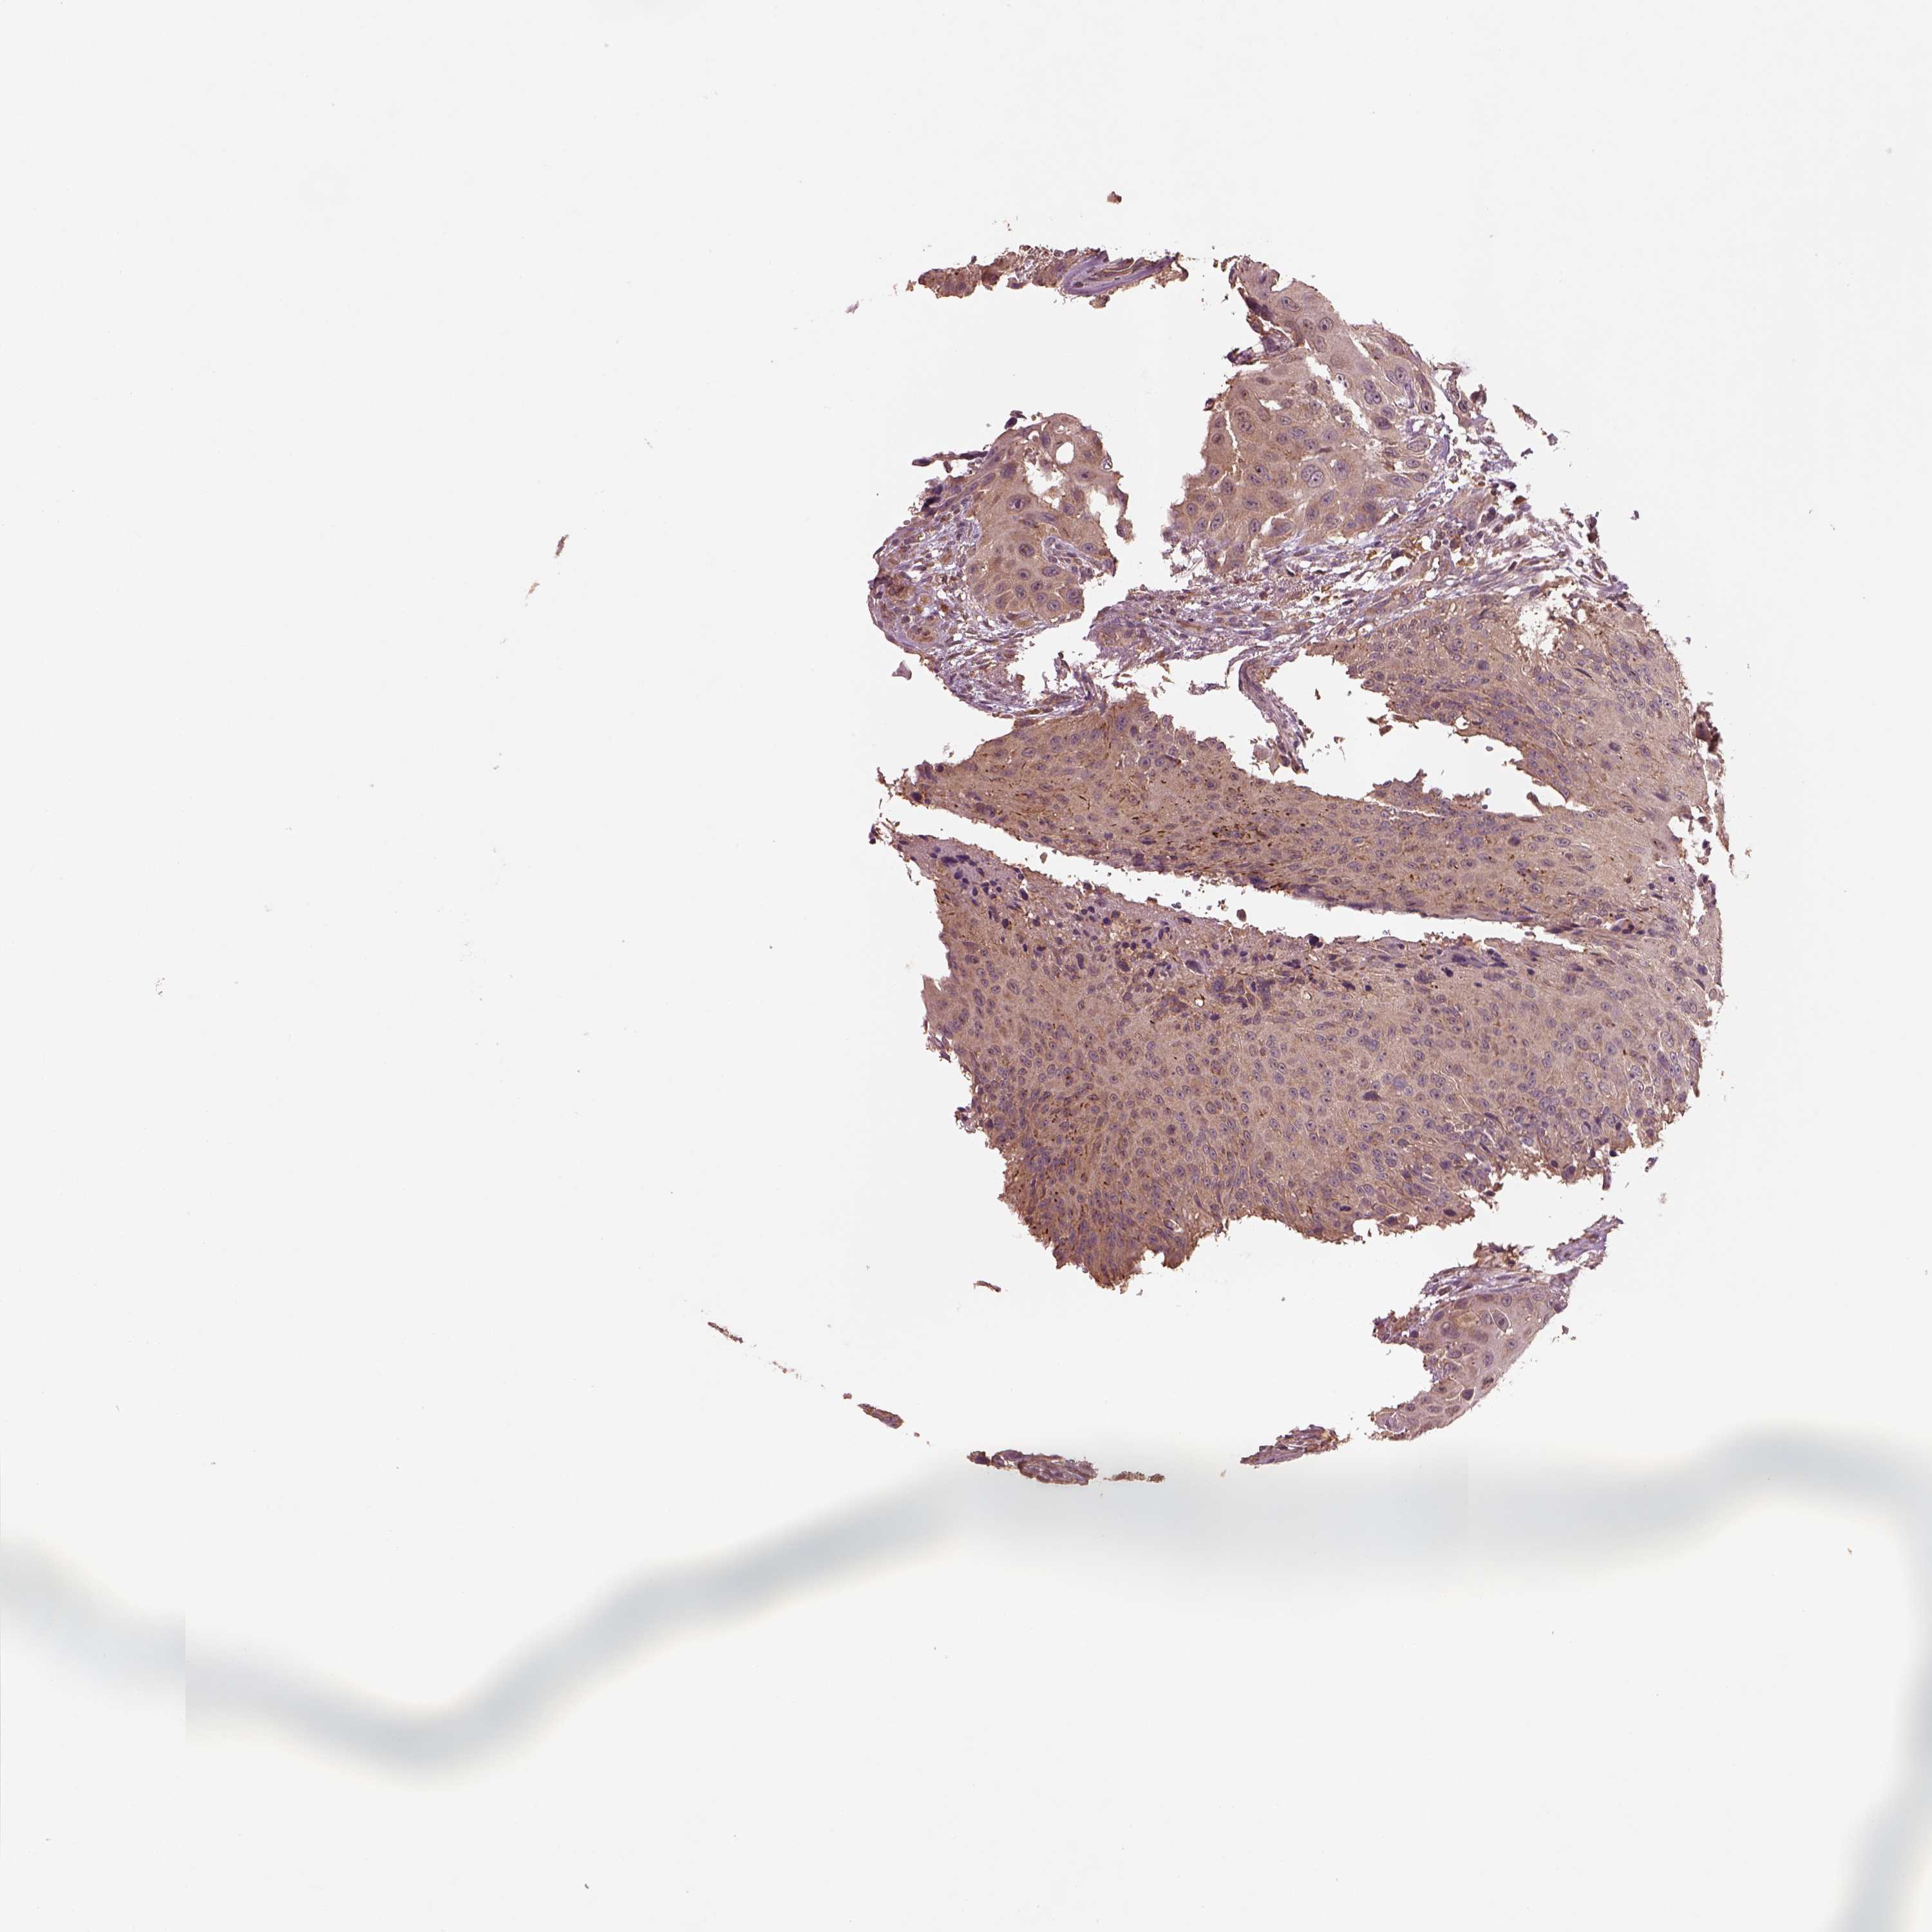

UROTHELIAL CANCER - Protein expressioni

A mouse-over function shows sample information and annotation data. Click on an image to view it in a full screen mode. Samples can be filtered based on level of antibody staining by selecting one or several of the following categories: high, medium, low and not detected. The assay and annotation is described here.

Note that samples used for immunohistochemistry by the Human Protein Atlas do not correspond to samples in the TCGA dataset.

Antibody stainingi

Antibody staining in the annotated cell types in the current human tissue is reported as not detected, low, medium, or high, based on conventional immunohistochemistry profiling in selected tissues. This score is based on the combination of the staining intensity and fraction of stained cells.

Each image is clickable and will lead to virtual microscopy that enables deeper exploration of all samples and also displays staining intensity scores, fraction scores and subcellular localization as well as patient and tissue information for each sample.

Antibody HPA071341

Antibody CAB004602

Staining

High

Medium

Low

Not detected

Intensity

Strong

Moderate

Weak

Negative

Quantity

>75%

75%-25%

<25%

None

Location

Nuclear

Cytoplasmic/membranous

Cytoplasmic/membranous,nuclear

Urothelial carcinoma, High grade

Urothelial carcinoma, NOS

Urothelial carcinoma, Low grade